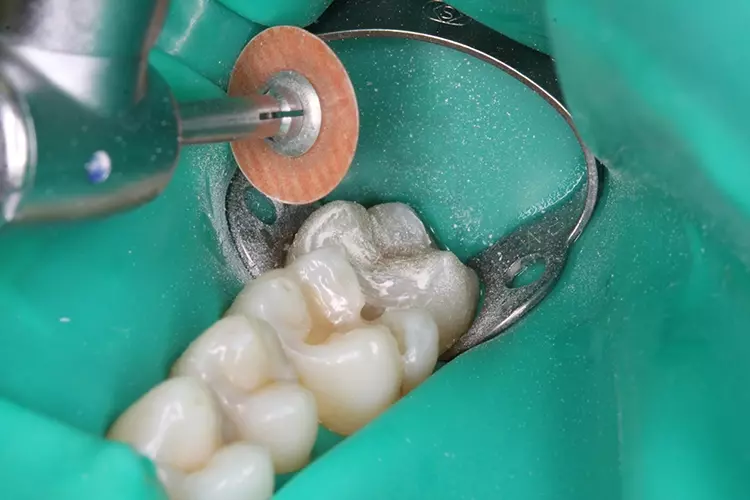

Die Exkavation der Karies, Primärpräparation und Randglättung an den Zähnen 26 und 27 sollten ohne Kofferdam erfolgen. Nach Anlegen des Kofferdams kann mit der adhäsiven Füllungstherapie begonnen werden (Abb. 3).

Die dünne Teilmatrize für Molaren für die Füllung an Zahn 27 (bombierte Teilmatrize Quickmat Deluxe 0,04 x 6,4 mm, Polydentia) ließ sich leicht adaptieren und zervikal abdichten (Abb. 4). Die Oberfläche der Kavität soll nach der Anwendung mit einem Adhäsiv (Futurabond U, VOCO) zunächst dünn mit einem fließfähigen Nanohybrid-Ormocer-Komposit (Admira Fusion Flow, VOCO) überschichtet werden.